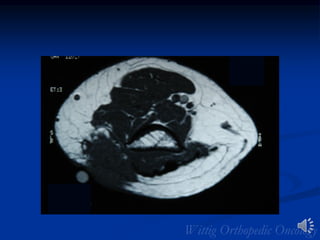

MFH Foot

MFH of Foot